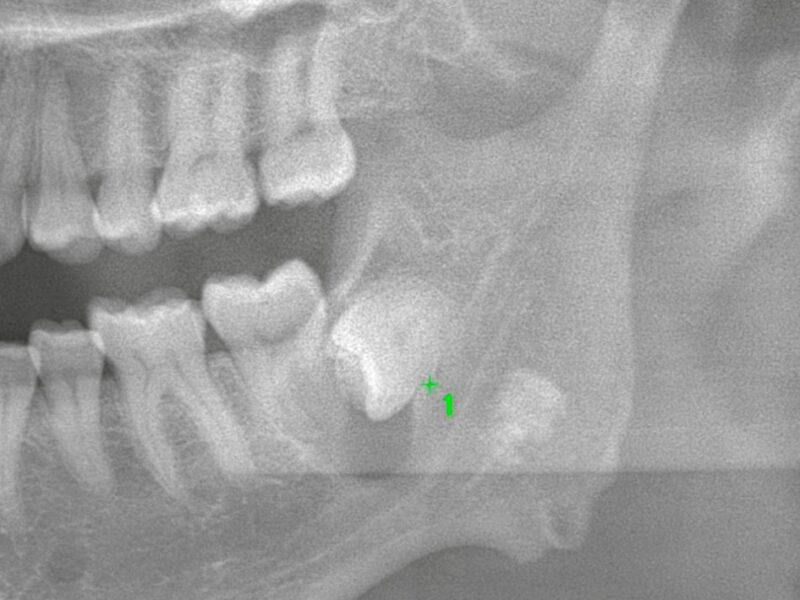

特徴4高精度診断を可能にする「歯科用CT」 -